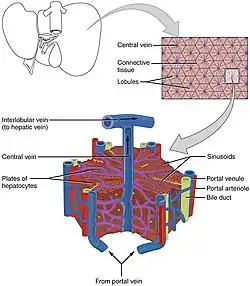

The liver is connected to two large blood vessels: the hepatic artery and the portal vein. The hepatic artery carries oxygen-rich blood from the aorta via the celiac trunk, whereas the portal vein carries blood rich in digested nutrients from the entire gastrointestinal tract and also from the spleen and pancreas.[8] These blood vessels subdivide into small capillaries known as liver sinusoids, which then lead to hepatic lobules.

Hepatic lobules are the functional units of the liver. Each lobule is made up of millions of hepatic cells (hepatocytes), which are the basic metabolic cells. The lobules are held together by a fine, dense, irregular, fibroelastic connective tissue layer extending from the fibrous capsule covering the entire liver known as Glisson's capsule after British doctor Francis Glisson.[4] This tissue extends into the structure of the liver by accompanying the blood vessels, ducts, and nerves at the hepatic hilum. The whole surface of the liver, except for the bare area, is covered in a serous coat derived from the peritoneum, and this firmly adheres to the inner Glisson's capsule.

Microscopic anatomy

Microscopically, each liver lobe is seen to be made up of hepatic lobules. The lobules are roughly hexagonal, and consist of plates of hepatocytes, and sinusoids radiating from a central vein towards an imaginary perimeter of interlobular portal triads.[22] The central vein joins to the hepatic vein to carry blood out from the liver. A distinctive component of a lobule is the portal triad, which can be found running along each of the lobule's corners. The portal triad consists of the hepatic artery, the portal vein, and the common bile duct.[23] The triad may be seen on a liver ultrasound, as a Mickey Mouse sign with the portal vein as the head, and the hepatic artery, and the common bile duct as the ears.[24]

Histology, the study of microscopic anatomy, shows two major types of liver cell: parenchymal cells and nonparenchymal cells. About 70–85% of the liver volume is occupied by parenchymal hepatocytes. Nonparenchymal cells constitute 40% of the total number of liver cells but only 6.5% of its volume.[25] The liver sinusoids are lined with two types of cell, sinusoidal endothelial cells, and phagocytic Kupffer cells.[26] Hepatic stellate cells are nonparenchymal cells found in the perisinusoidal space, between a sinusoid and a hepatocyte.[25] Additionally, intrahepatic lymphocytes are often present in the sinusoidal lumen.[25]

Blood flows through the liver sinusoids and empties into the central vein of each lobule. The central veins coalesce into hepatic veins, which leave the liver and drain into the inferior vena cava.[41]